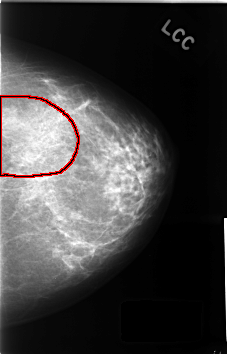

C_0435_1.LEFT_CC

LEFT_CC LINES 4600 PIXELS_PER_LINE 2944 BITS_PER_PIXEL 12 RESOLUTION 50 OVERLAY

FILE: C_0435_1.LEFT_CC.OVERLAY

TOTAL_ABNORMALITIES 1

ABNORMALITY 1

LESION_TYPE MASS SHAPE ASYMMETRIC_BREAST_TISSUE MARGINS N/A

ASSESSMENT 3

SUBTLETY 5

PATHOLOGY BENIGN_WITHOUT_CALLBACK

TOTAL_OUTLINES 1

BOUNDARY